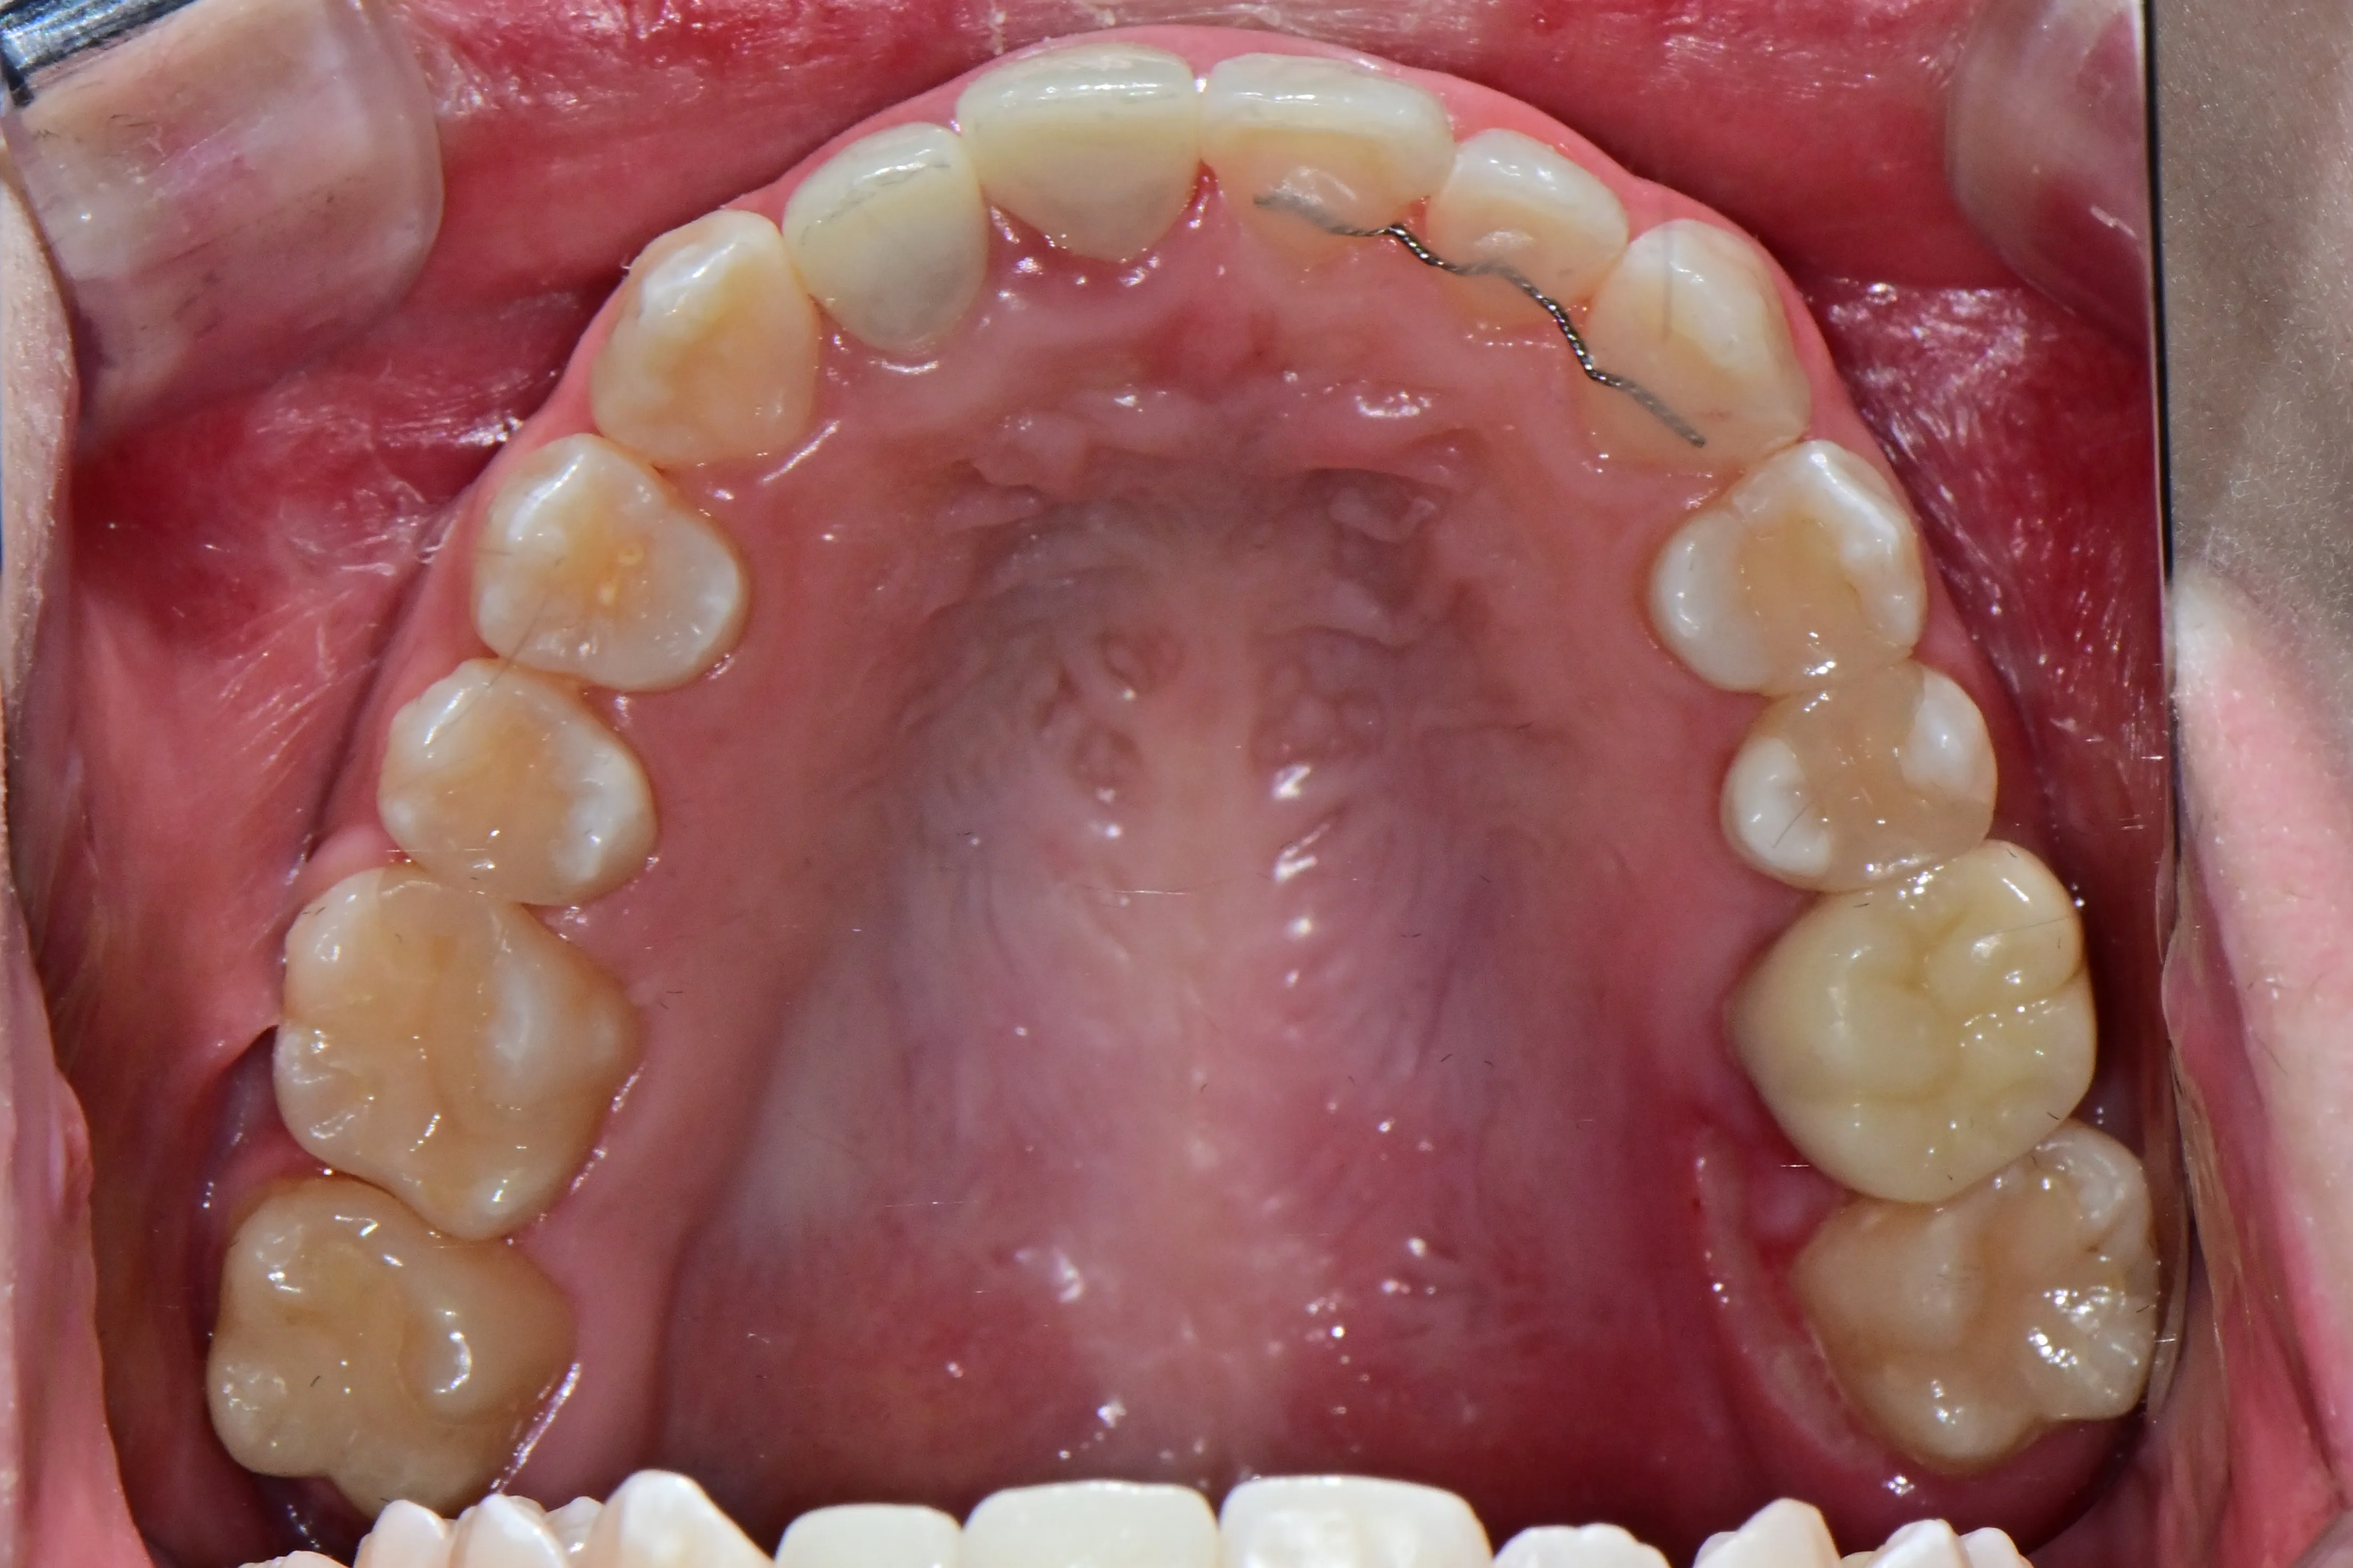

만 21세 환자로, 기존에 사고로 여러 치아를 다치고 상실한 상태로 매우 심한 교합무너짐이 있었습니다.

치료전 (Before)